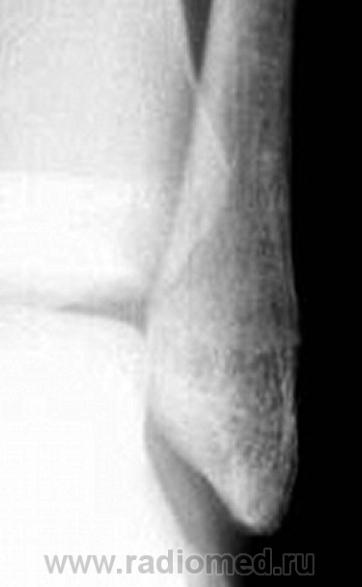

А как на счет малоберцовой кости ? Не было ли тут небольшого переломчика?

киста пяточной кости и вальгусная деформация голеностопного сустава

По поводу вальгусной деформации, а не в укладке ли дело?

а это снимок справа